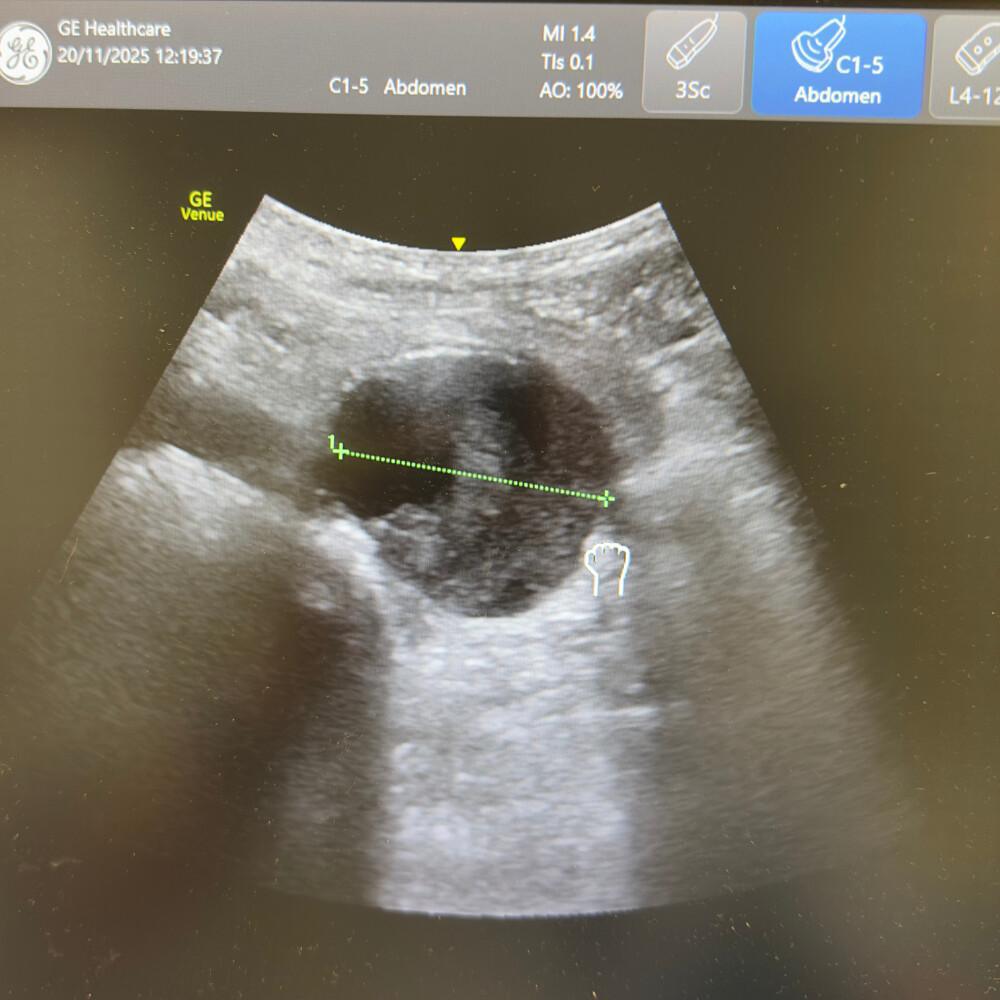

Le diamètre externe-externe doit être mesuré perpendiculairement au faisceau, sans compression.

- Diamètre normal : < 3 cm.

- Anévrysme fusiforme ou sacculaire : dilatation > 3 cm, souvent avec calcifications pariétales.

🚨 Un AAA > 5,5 cm ou douloureux = urgence chirurgicale absolue.